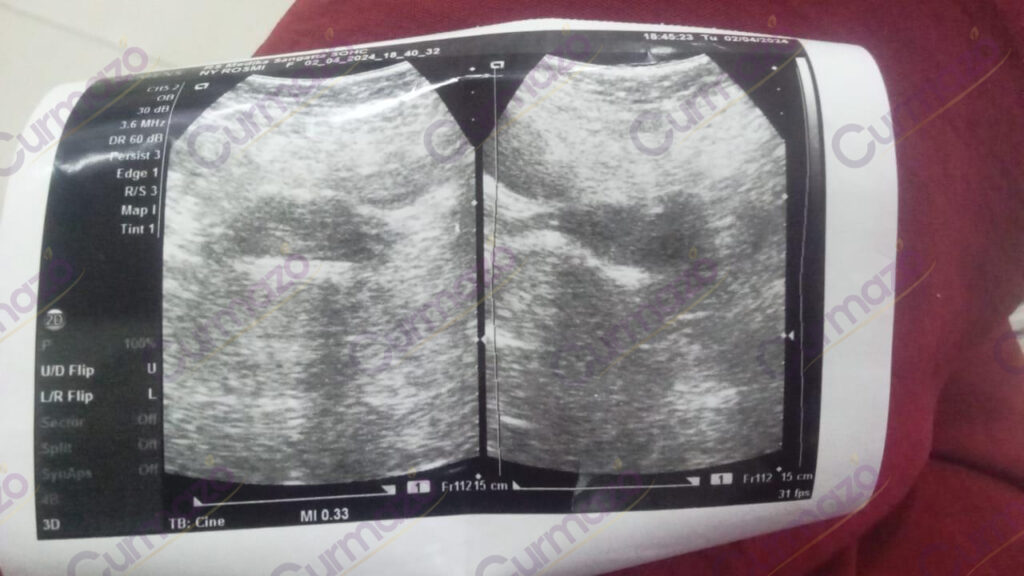

Sebelum Minum Herbal

Pada 2 Maret 2024, saya mengalami haid yang berkepanjangan disertai pendarahan, dan sering ingin buang air kecil. Lalu saya periksakan ke dokter, hasilnya ada miom 5.32 cm dan dianjurkan untuk operasi namun saya menolak karena takut.

Lalu saya mencari solusi lain untuk kesembuhan saya, akhirnya saya menemukan Curmazo & K-Muricata di Facebook. Saya sangat tertarik untuk mencobanya karena ini alami tanpa efek samping dan sudah banyak yang coba.

24 Maret 2024, saya mulai rutin konsumsi Curmazo & K-Muricata dengan dipandu oleh herbalisnya.

Hasilnya, setelah 2 bulan pengobatan saya merasa ada perubahan baik di tubuh saya. Siklus haid kembali normal, sudah tidak ada pendarahan, dan perut tidak terasa begah lagi.

2 Mei 2024, saya periksakan kembali hasilnya alhamdulillah miom hilang total. Sekarang saya bisa menjadi istri sekaligus ibu yang sehat & bahagia.